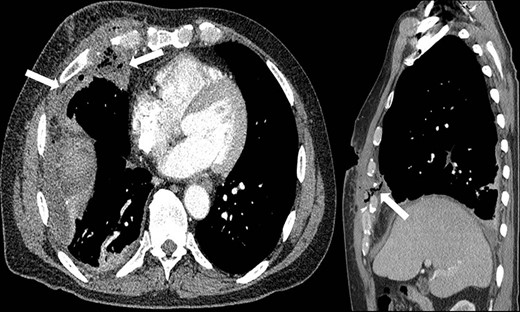

Representative coronal and sagittal images of the patient’s initial chest CT scan confirming the intrathoracic location of the foreign body with associated scatter due to its metallic contents.

A 59-year-old man was transferred acutely from another hospital for evaluation of a penetrating thoracic injury. The patient reportedly had been shot twice with a bean bag gun and sustained injuries to the right chest and flank during an altercation with police officers. The patient was breathing comfortably and normotensive, and his GCS was 15. He had a history of unprovoked pulmonary embolism and was taking apixaban. There was a 2-cm circular wound through the skin just superior to the right nipple and a 5-cm area of ecchymotic but intact skin over the right flank. A chest X-ray showed a 2-cm object with metallic density overlying the right thoracic cavity (Fig. 1). A chest CT showed the object in close proximity to the right atrium, right internal mammary artery and right middle lobe (Fig. 2). Additionally, a small amount of effusion consistent with hemothorax was present, for which a chest tube was placed. The patient was admitted for chest tube management and pain control, on the assumption that the metallic foreign body did not warrant operative removal.